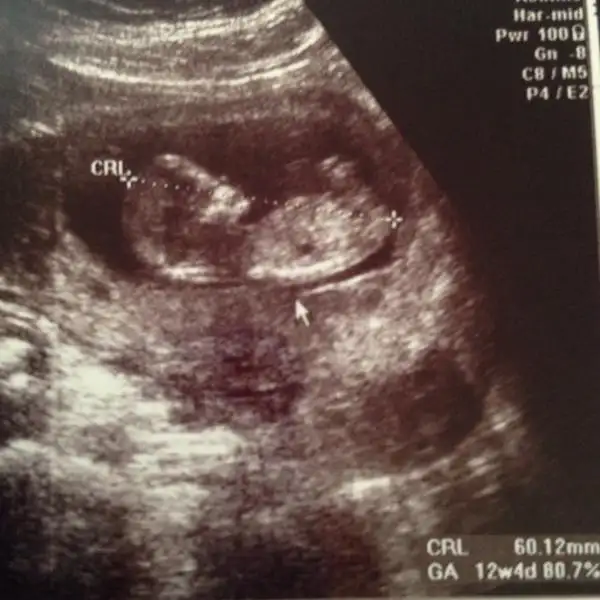

Biz kontrolden geldiiikk 2 li test olduk

Ölçümleri gayet iyi ve normal şükürler olsun. Kan verdim yarın alıcam sonucunu doktorum arayıp söylicek.

Kıpır kıpırdı minnağım açmış koca göbişimi oohhh keyif yapıyordu bozduk keyfini kıyamam.

12+1 olmamız lazımdı bir aydır iki gün önden gidiyordu şimdi 3 gün önden gidiyor 12+4 görünüyor :) iri bebiş olcak dedi doktor babası çünkü 1.90 babaya çekmiş dedi :)

Umarım kan sonucumuzda iyi çıkar. Cinsiyet söylemiyo dr ancak 1 ay sonra dedi nası bekliceksem fotodan nubu da seçemiyorum :/

Minik limonum teyzelerine merhaba diyoor :)